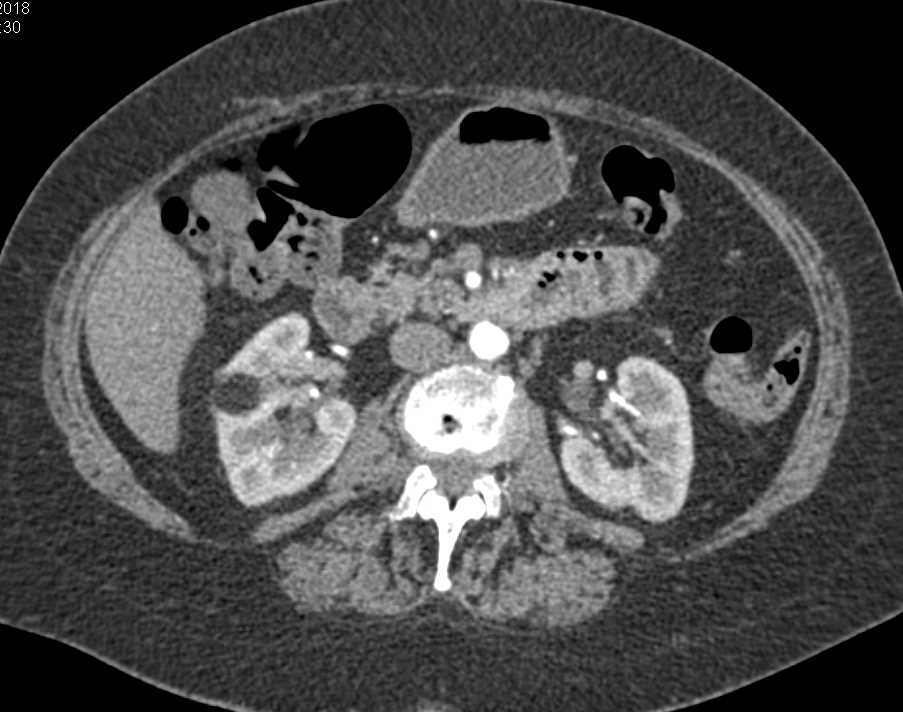

Incidental Clear Cell Renal Cell Carcinoma (RCC) Lower Pole Right Kidney